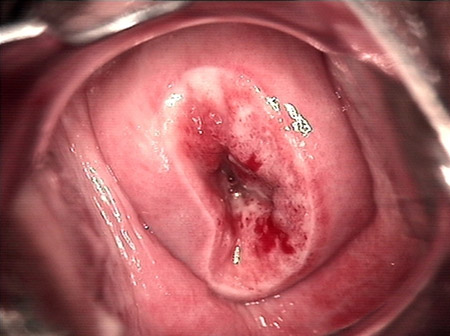

• CIN 2-3 leep術(shù)后CIN 2-3 leep術(shù)后

• CIN 2-3 修復(fù)后CIN 2-3 修復(fù)后